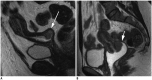

Magnetic resonance imaging is the optimal modality for pelvic imaging. It is based on T2-weighted magnetic resonance (MR) sequences allowing uterine and vaginal cavity assessment as well as rectal evaluation. Anatomical depiction of these structures may benefit from distension, and conditions either developing inside the lumen of cavities or coming from the outside may then be better delineated and localized. The need for distension, either rectal or vaginal, and the way to conduct it are matters of debate, depending on indication for which the MR examination is being conducted. In this review, we discuss advantages and potential drawbacks of this technique, based on literature and our experience, in the evaluation of various gynecological and rectal diseases.